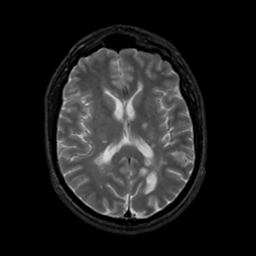

MR Study #7, March 24, 1991 -- Slice #28